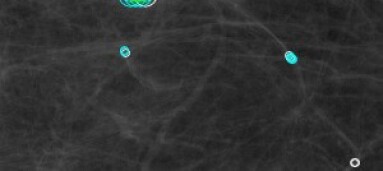

Comparison to the a contrario method of Grosjean and Moisan [4]. This a contrario method is designed to detect spots in colored noise textures, and was applied to the detection of tumors in mammographies. This detection algorithm is the only other one computing NFAs, and we can directly compare them to ours. The detection results on a real mammography (having a tumor) are shown in Figure 3. With our method the tumor is detected with a much significant NFA (NFA of whereas in [4] NFA of ). Our self-similar anomaly detection method shows fewer false detections, actually corresponding to rare events like the crossings of arterials.